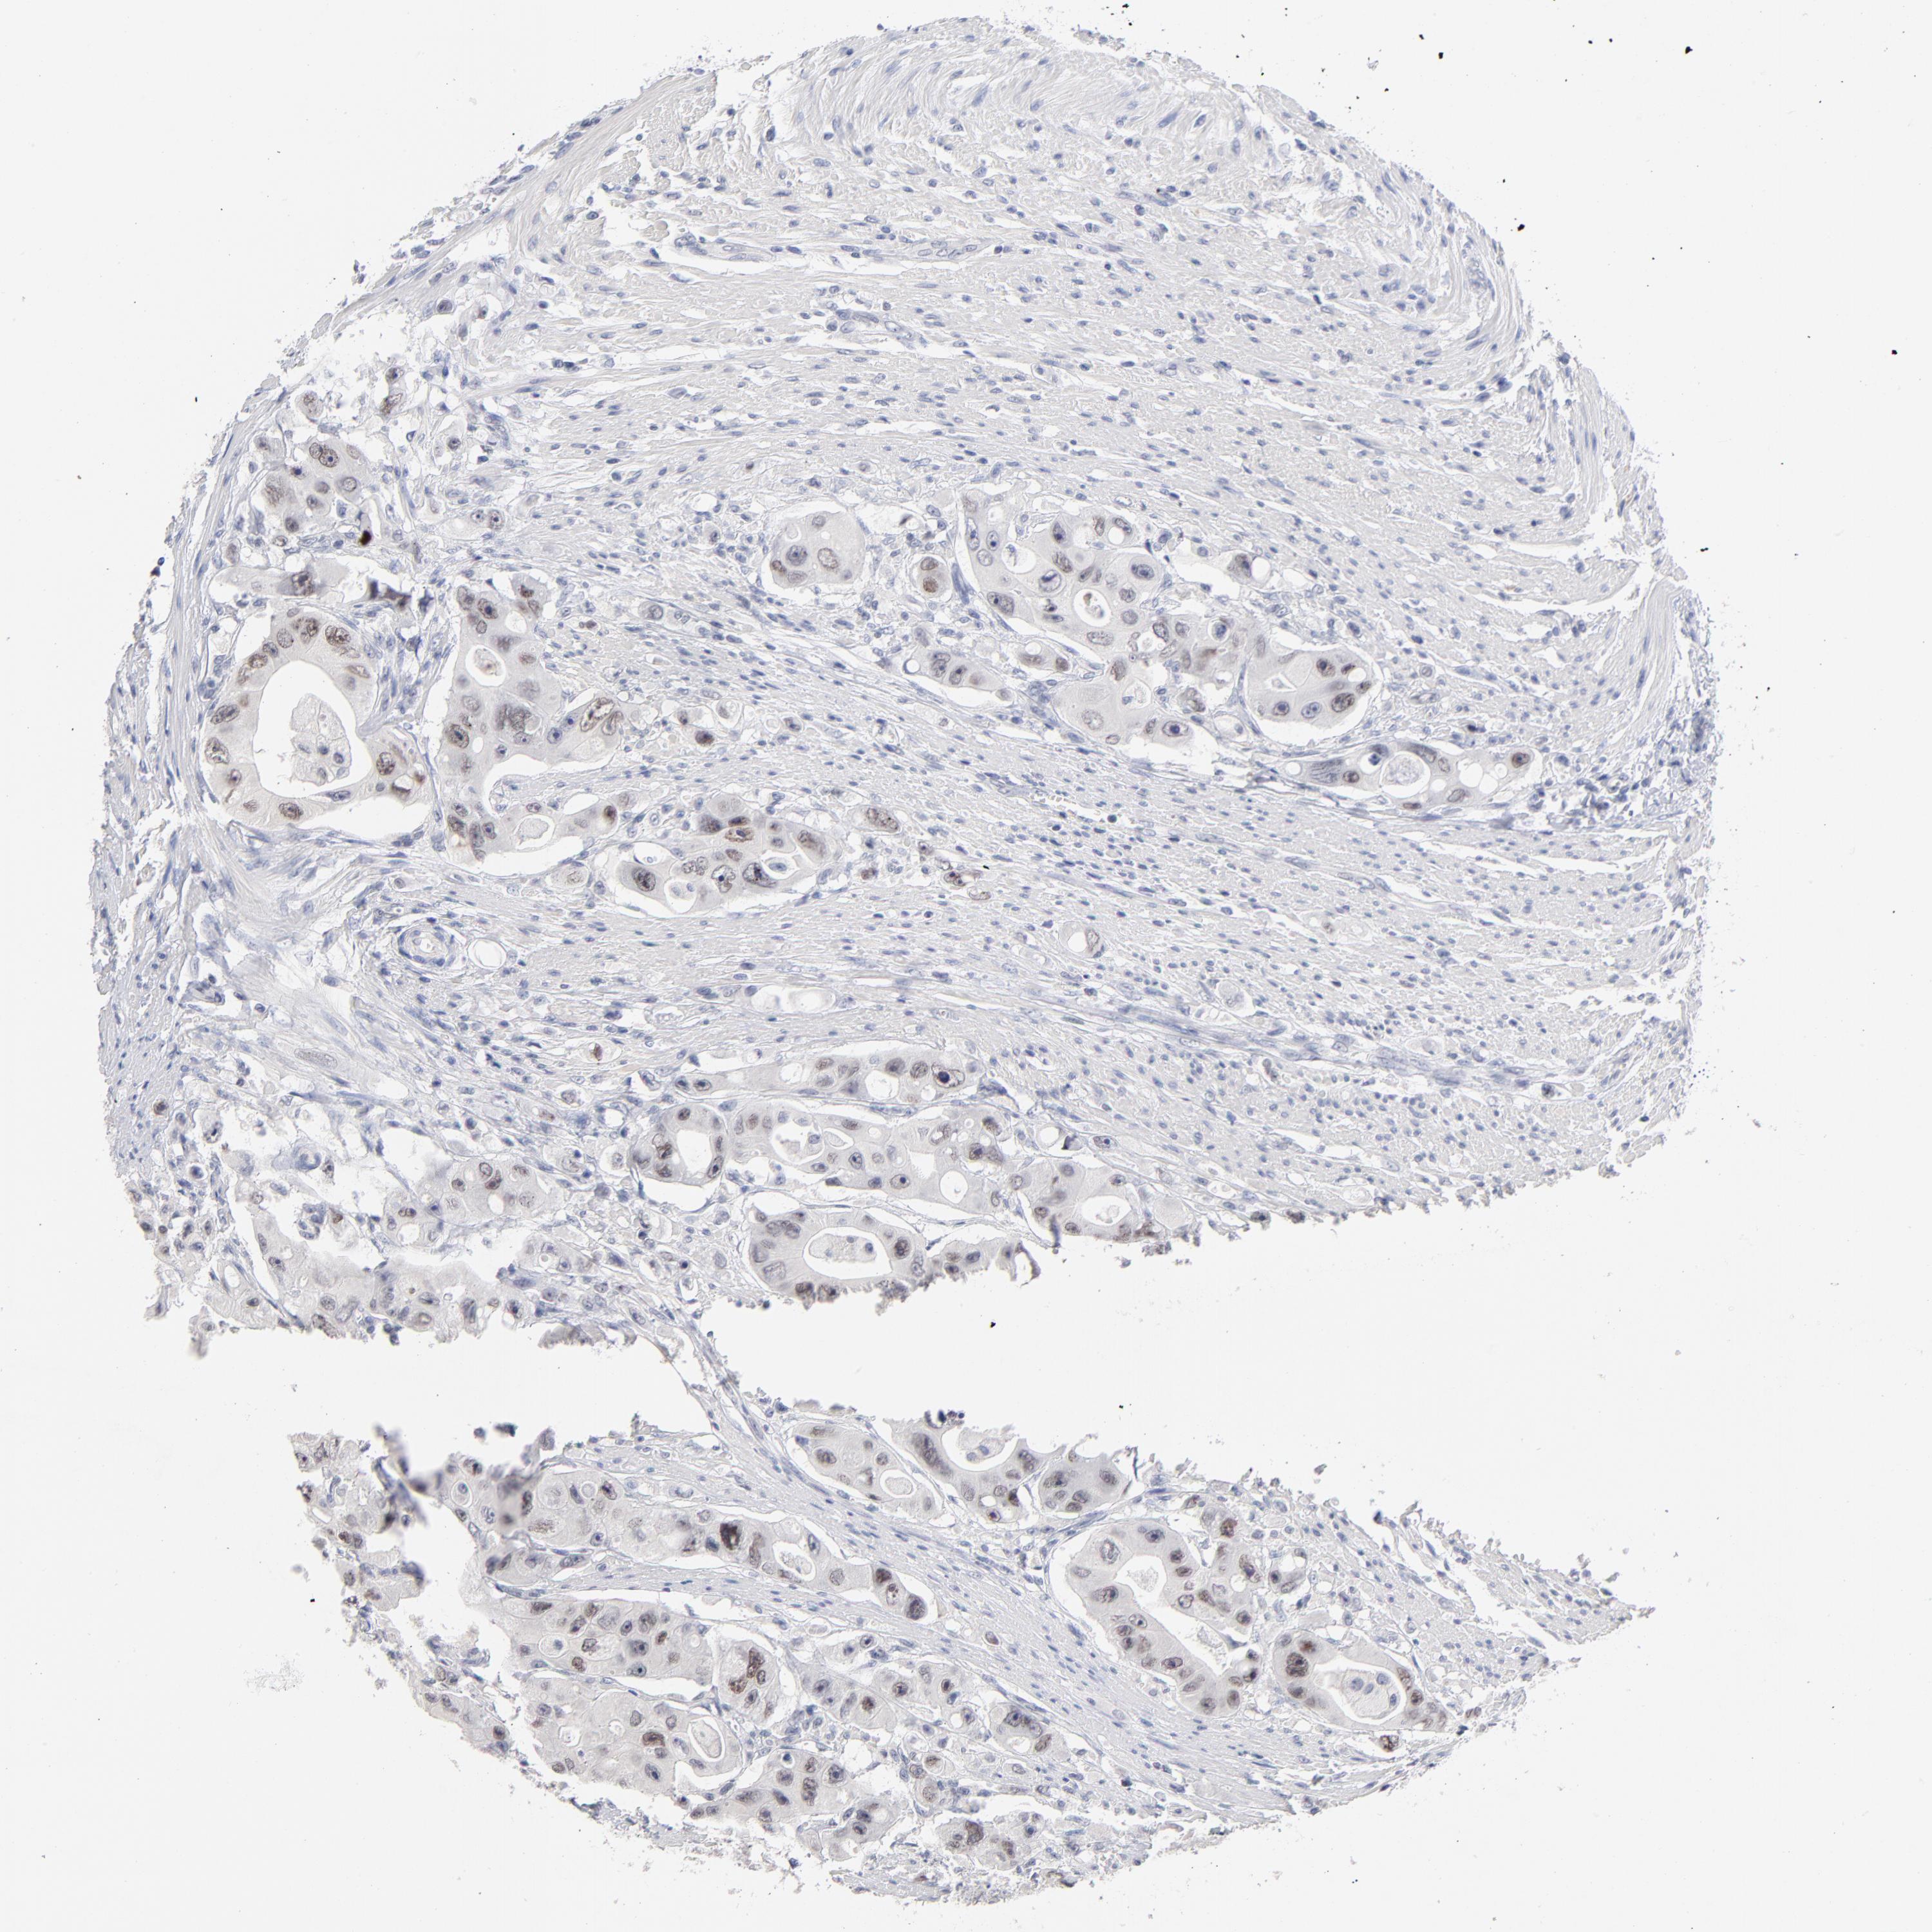

CANCER COLORECTAL CANCER Show tissue menu

Colorectal cancer

Human cancer

Colon adenocarcinoma

Rectum adenocarcinoma